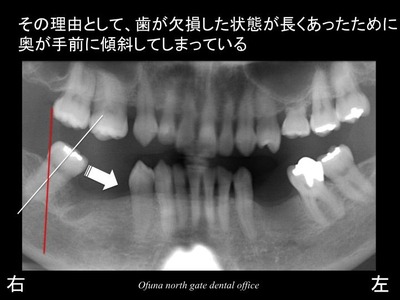

その理由として、

歯が欠損した状態が長くあったために

奥歯が手前に傾斜してしまったのです。